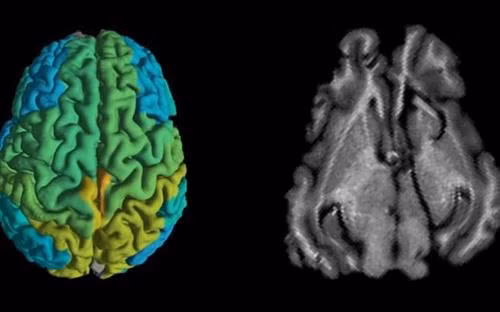

Theo công trình nghiên cứu được đăng trên tạp chí Nature Communications ngày 30/7, các nhà khoa học thuộc Đại học Hebrew ở Jerusalem cho biết đã phát triển một mô hình toán học có thể thu thập được thông tin về những thay đổi phân tử trong não bộ từ hình ảnh MRI. Nhà nghiên cứu Aviv Mezer, trưởng nhóm nghiên cứu, nhấn mạnh "điều này cung cấp cho chúng ta những thông tin mới về não bộ". Ông cũng nói rằng "trong tương lai, chúng ta sẽ cần nghiên cứu xem mô hình này có thể nhạy cảm với các bệnh thoái hóa thần kinh hay không", đồng thời bày tỏ hy vọng mô hình này sẽ trở thành một công cụ giúp các bác sĩ xác định liệu một bệnh nhân chỉ đơn thuần già đi hay mắc các bệnh thoái hóa thần kinh như Alzheimer hay Parkinson.

Cũng theo nhà nghiên cứu Mezer, kỹ thuật MRI mới này cũng sẽ giúp các chuyên gia y tế hiểu rõ hơn về quá trình lão hóa của não bộ ở mỗi độ tuổi. Ở những đối tượng trẻ tuổi, các nhà nghiên cứu thấy được những thay đổi lớn hơn trong cấu tạo phân tử của chất xám so với những người cao tuổi. Ông Mezer kỳ vọng mô hình này có thể giúp các bác sĩ so sánh các lần chụp não bộ từ cùng một bệnh nhân qua thời gian, cũng như phân biệt giữa mô não khỏe và mô bệnh mà không cần dùng đến các biện pháp xâm lấn nguy hiểm khác, như sinh thiết mô não hiện đang được thực hiện trong các trường hợp có khối u não. Như vậy, nhờ vào kỹ thuật mới không xâm lấn, bệnh nhân sẽ có nhiều cơ hội được chẩn đoán chính xác sớm hơn, đẩy nhanh quá trình điều trị cũng như đảm bảo chất lượng cuộc sống được cải thiện hơn.

Mặc dù nghiên cứu này chỉ tập trung vào việc đánh giá hình ảnh não bộ, song các nhà khoa học tin tưởng có thể điều chỉnh và áp dụng kỹ thuật MRI mới này cho các cơ quan khác trong cơ thể.